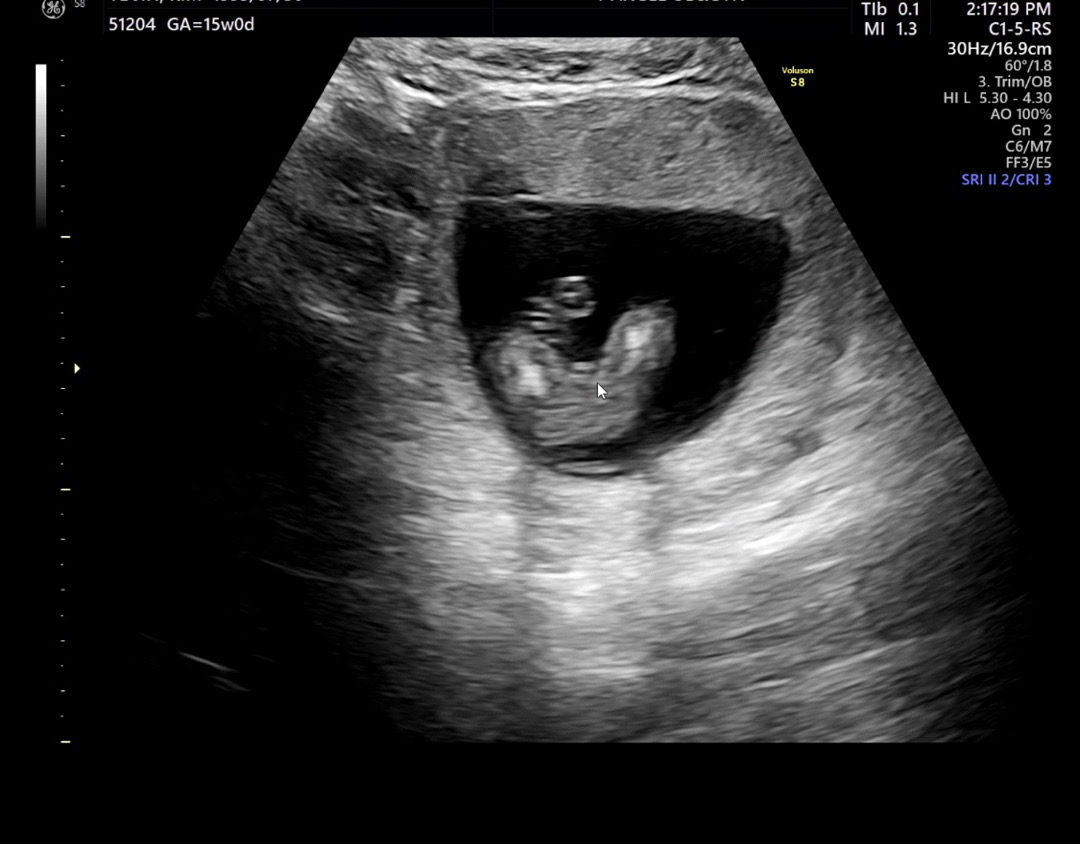

다리사이 저거 탯줄인가요? 고추인가여?

이거 탯줄인가요? 탯줄인지 뭔지 모르겠다하시는데 엄마쪽같다하셨다가 잘모르겠다고하시면서 60대40이래요 ㅠㅠ